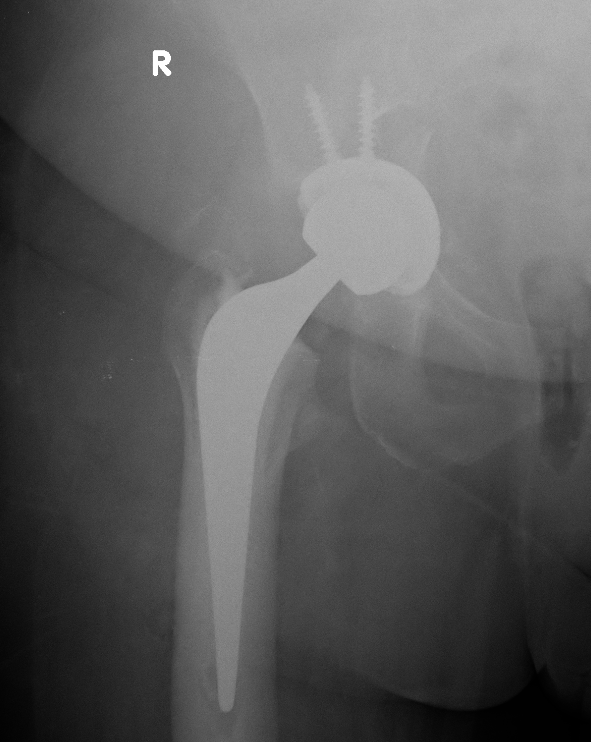

Postoperative acetabular fracture treated with double posterior plating